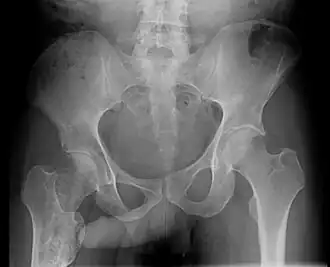

Positive John Thomas sign in patient with right femoral enchondroma

The John Thomas sign,[1] also known as the Throckmorton sign,[2] is a slang or joke term used in the field of radiology. It refers to the position of a penis as it relates to pathology on an X-ray of a pelvis. When the penis (visible on the X-ray as a shadow) points towards the same side as a unilateral medical condition such as a broken bone, this is considered a "positive John Thomas sign," and if the shadow points to the other side, it is a "negative John Thomas sign."[3]

Studies have shown that the "sign" is no better than chance at identifying the location of a hip fracture.[4][5] In those cases where the John Thomas sign is positive, it has been proposed that a person with a displaced hip fracture may try to lie on the injured side to immobilize the fracture and reduce pain; the penis then inclines toward the downward (injured) side.[6]